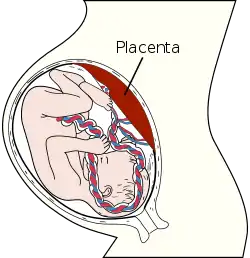

The placenta (pl.: placentas or placentae) is a temporary embryonic and later fetal organ that begins developing from the blastocyst shortly after implantation. It plays critical roles in facilitating nutrient, gas and waste exchange between the physically separate maternal and fetal circulations, and is an important endocrine organ, producing hormones that regulate both maternal and fetal physiology during pregnancy.[1] The placenta connects to the fetus via the umbilical cord, and on the opposite aspect to the maternal uterus in a species-dependent manner. In humans, a thin layer of maternal decidual (endometrial) tissue comes away with the placenta when it is expelled from the uterus following birth (sometimes incorrectly referred to as the 'maternal part' of the placenta). Placentas are a defining characteristic of placental mammals, but are also found in marsupials and some non-mammals with varying levels of development.[2]

Structure

Placental mammals, including humans, have a chorioallantoic placenta that forms from the chorion and allantois. In humans, the placenta averages 22 cm (9 inch) in length and 2–2.5 cm (0.8–1 inch) in thickness, with the center being the thickest, and the edges being the thinnest. It typically weighs approximately 500 grams (just over 1 lb). It has a dark reddish-blue or crimson color. It connects to the fetus by an umbilical cord of approximately 55–60 cm (22–24 inch) in length, which contains two umbilical arteries and one umbilical vein.[12] The umbilical cord inserts into the chorionic plate (has an eccentric attachment). Vessels branch out over the surface of the placenta and further divide to form a network covered by a thin layer of cells. This results in the formation of villous tree structures. On the maternal side, these villous tree structures are grouped into lobules called cotyledons. In humans, the placenta usually has a disc shape, but size varies vastly between different mammalian species.[13]